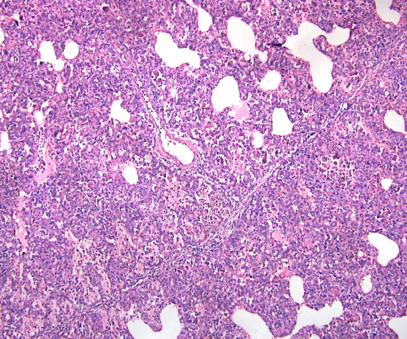

左图,肺泡内巨噬细胞的损伤可以认为是蓝耳特异性的显微病变

中图和右图,严重的间质性肺炎也基本可以认为是蓝耳引起的,虽然间质性肺炎意味着病毒性疾病,但是别的别的病毒性疾病可能很难引起这种典型病变

但是典型的显微病变不是每个蓝耳感染个体都能看到